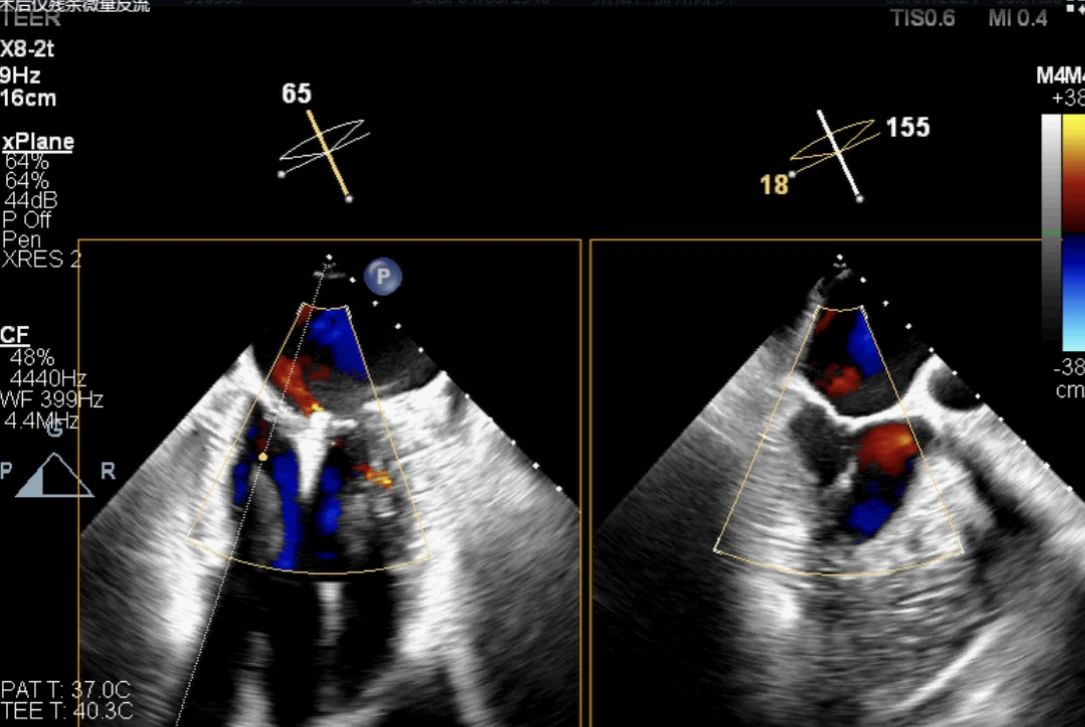

術前經食道超聲提示以P2區為主的二尖瓣中大量反流 術前心臟超聲結果

高質量的TEE圖像對于手術成功至關重要。楊婭主任分析了患者的心臟結構特點,同時聯合醫學影像科主任王寧團隊進行食道實時三維評估,術前充分評估反流量,反流位置,瓣口面積,瓣葉情況。實際發現反流量4+,主要以P2區為主,瓣口面積5.42cm2。

術后僅殘余微量反流